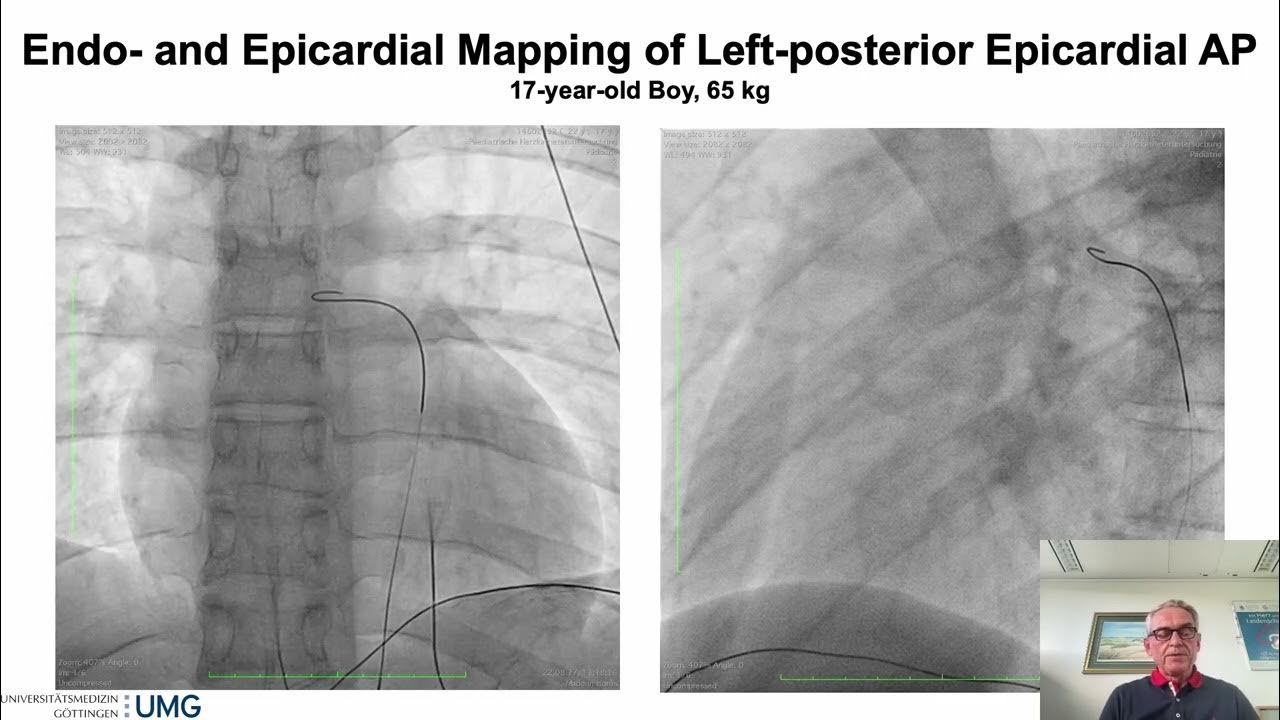

From www.youtube.com

How to Approach Epicardial Accessory Pathways YouTube Accessory Pathway Types Accessory pathways between the atria and ventricles may take a number of anatomical forms. Additional or accessory av pathway. The most common type (figure 3a) results from an electric circuit that travels from the atria through the av node. The two main forms of tachyarrhythmias that occur due to accessory pathways are discussed separately — see. Accessory atrioventricular pathways are. Accessory Pathway Types.